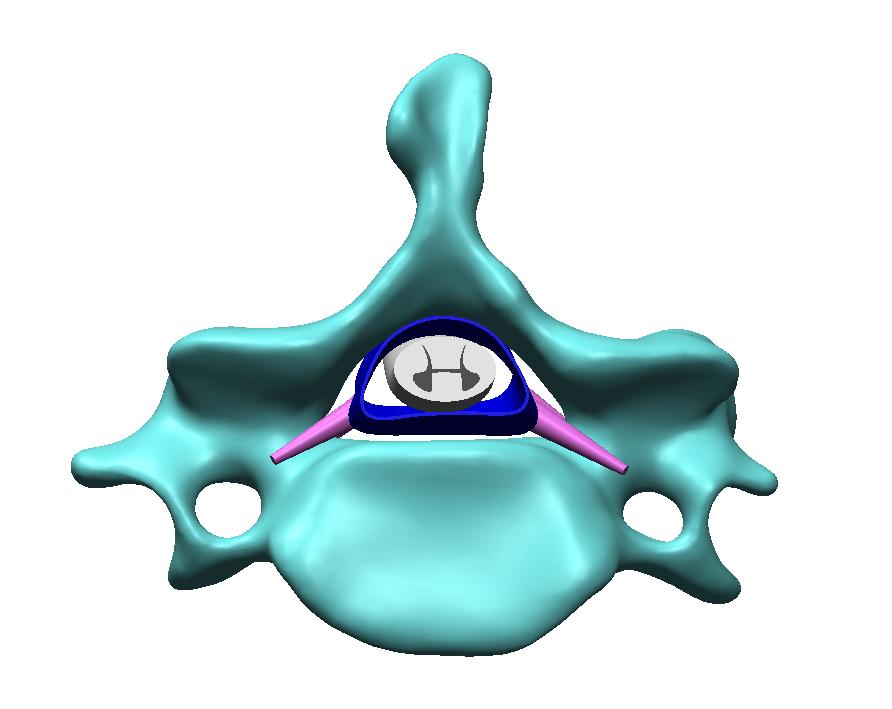

METHODS: A 27-year-old Asian male patient with cervical spondylotic radiculopathy caused by left posterior cervical disc herniation compressing the nerve root was recruited. The CT scan data of the skull and cervical spine were extracted to construct a finite element model of the skull and the whole cervical spine. After the model was verified, the key parameters of cervical rotation manipulation and cervical rotation-traction manipulation were loaded into the model, and the effects of these two manipulations on the stress of the intervertebral disc, facet joint, spinal cord and nerve root, disc displacement, as well as the volume of the cervical intervertebral foramen and other indexes were compared and analyzed.

RESULTS AND CONCLUSION: (1) In terms of Von-Mise stress, the maximum stresses of cervical rotation manipulation on the annulus fibrosus of the intervertebral disc, nucleus pulposus and facet joint were 0.903, 0.139, and 2.186 MPa, respectively, which were increased by 18%, 13%, and 30% compared with those of cervical rotation-traction manipulation (0.765, 0.123, and 1.682 MPa). The maximum stress of the spinal cord and nerve root was 2.547 Mpa, which was 7% lower than that of cervical rotation-traction manipulation (2.738 MPa). (2) In terms of displacement, the maximum forward displacement of the side with intervertebral disc herniation under cervical rotation manipulation was 1.067 mm, which was 11.1% more than that under cervical rotation-traction manipulation (0.960 mm). (3) In terms of the change in the volume of the intervertebral foramen, both manipulations led to an increase compared with before the manipulation. The volume increased by 15.5% under rotation manipulation and 19.8% under rotation-traction manipulation, and the latter had a more significant effect on expanding the volume of the intervertebral foramen. (4) It is concluded that cervical rotation manipulation has an advantage in promoting the forward displacement of the herniated intervertebral disc, but it generates higher stress on the intervertebral disc and facet joint, and is likely to cause intervertebral disc injury. Cervical rotation-traction manipulation makes the spinal cord and nerve root bear slightly higher stress, but it can more effectively expand the volume of the intervertebral foramen and reduce the risk of intervertebral disc structural injury. In clinical treatment, the advantages and disadvantages of these two manipulations should be carefully weighed according to the specific condition of the patient, and the application should be rationally selected.